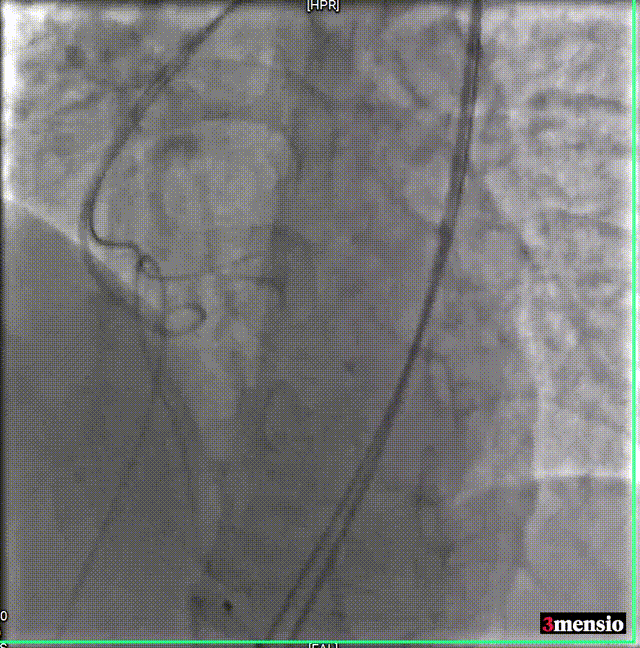

瓣膜释放至工作位评估

瓣膜脱钩

25mm球囊后扩

瓣膜最终形态

术后即刻评估

术后压差从78.3mmHg降至6.89mmHg,瓣膜正常工作,患者血流动力学即刻得到改善。